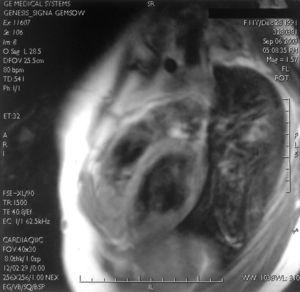

Se presentan 2 casos clínicos. El primero es una niña de 11 años remitida por arritmia, sin antecedentes personales y familiares de interés. Exploración física: arritmia cardíaca. Electrocardiograma y eje izquierdo: extrasistolia frecuente con imagen de BRIHH. La ecocardiografía mostró leve insuficiencia mitral y ventrículo derecho con hipocinesia de pared lateral. El Holter de 24 h reveló extrasistolia ventricular frecuente (5.878 con 18 pares de contracciones ventriculares prematuras). En la resonancia magnética (RM) cardíaca se observó aumento de la cavidad ventricular derecha, así como una clara alteración con infiltración grasa de la pared del ventrículo derecho. El examen dinámico mostró y confirmó una hipertrofia ventricular derecha (fig. 1). El segundo caso es una niña de 13 años que fue remitida por arritmia. Antecedentes personales y familiares sin interés. Exploración física: arritmia cardíaca. Electrocardiograma: extrasistolia ventricular bigeminada-trigeminada con morfología de BRIHH y eje izquierdo. Ecocardiografía normal. Holter de 24 h: extrasistolia ventricular frecuente (37.258 con 2.110 pares de contracciones ventriculares prematuras). La RM cardíaca mostró existencia de tejido graso intramiocárdico en cara diafragmática del ventrículo derecho.

Figura 1.RM que muestra aumento de cavidad ventricular derecha con infiltración grasa de la pared del ventrículo derecho.